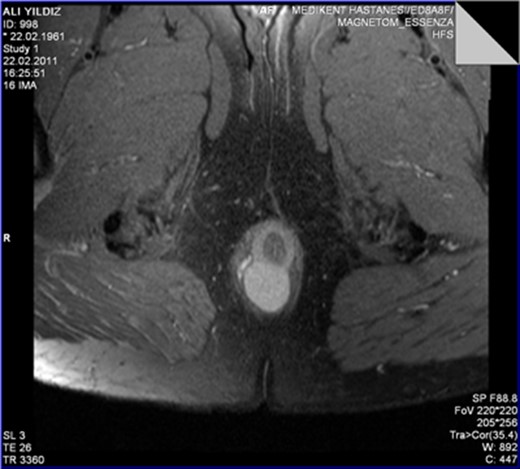

The MRI scan revealed a well-circumscribed homogeneous mass ovoid in shape, measuring 3.4 × 3.5 × 2.7 cm3 in diameter located in the intersphincteric plane, originating from the posterior aspect of the internal anal sphincter just in the midline, growing away from the lumen, displacing and stretching the external anal sphincter (Figs 1 and 2).

The leiomyoma originating from the internal anal sphincter growing far from the lumen stretching and pushing away the external anal sphincter.

The perinal fistula passing intersphincterically upwards in close relation to the leiomyoma without invasion.